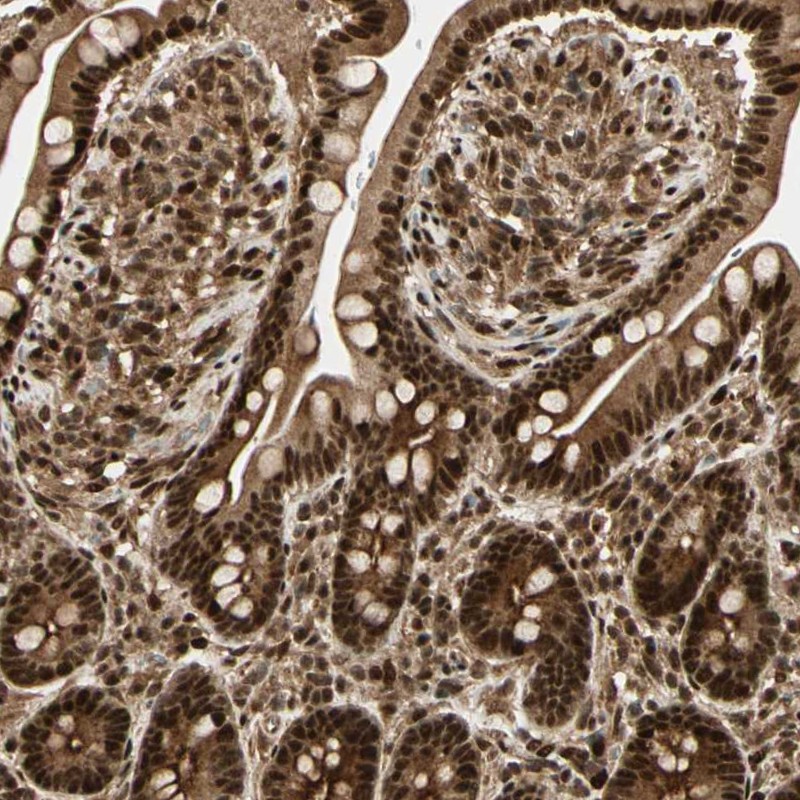

Immunohistochemical staining of human small intestine shows nuclear and cytoplasmic positivity in glandular cells.